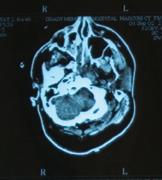

Berns believes a third culprit may share blame. He contends that teens suffer from a hyperactive reward system fueled by a deluge of dopamine. To test the theory, he is leading a study using functional magnetic resonance imaging (fMRI) to measure brain activity in the reward system of adolescents ages 12 to 17. Funded by the NIH, the four-year study will involve up to 200 participants. More than 50 teens have enrolled thus far.

While their brain activity is monitored using fMRI, participants complete different decision-making tasks, all of which involve weighing risks and rewards. The fMRI measures blood flow in the brain—a step beyond regular MRI, which captures the structure of the brain.